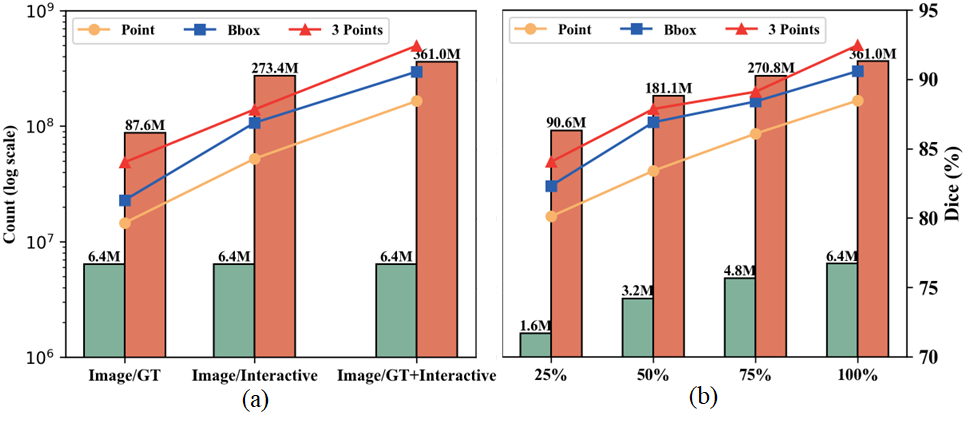

04 数据规模对IMIS-Net的影响

图7. 数据规模对IMIS-Net的影响

IMed-361M数据集是迄今为止最大、公开可用的多模态交互式医学图像分割数据集,包含640万张图像、8760万个ground truth和2.734亿个交互式掩码,平均每张图像56个掩码。该数据集覆盖14种成像模态和204个分割目标,包括各主要器官及病变,涉及人体几乎所有部位。图像分辨率主要集中在256×256到1024×1024之间,确保研究场景的广泛适应性,大多数掩模占用的图像面积不足2%,反映了医学分割的细粒度特性。手动去除不相关的标注并应用过滤策略,仅保留有效掩模,从而增强模型在不同场景中的适应能力。

前所未有的数据规模与掩码数量